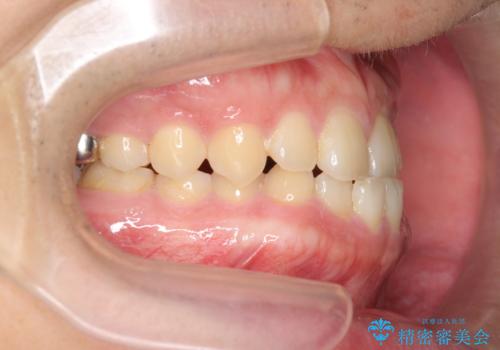

- 前歯の噛み合わせが反対になっていること、前歯の見た目の改善を希望され来院されました。

詳細な矯正検査の結果、顎の歪みが見られたため大きく歯を動かす治療ではなく前歯を主に並べることで前歯の前後関係を改善していきます。

前歯を主に動かす部分矯正であることからマウスピース矯正インビザラインによる治療を計画します。